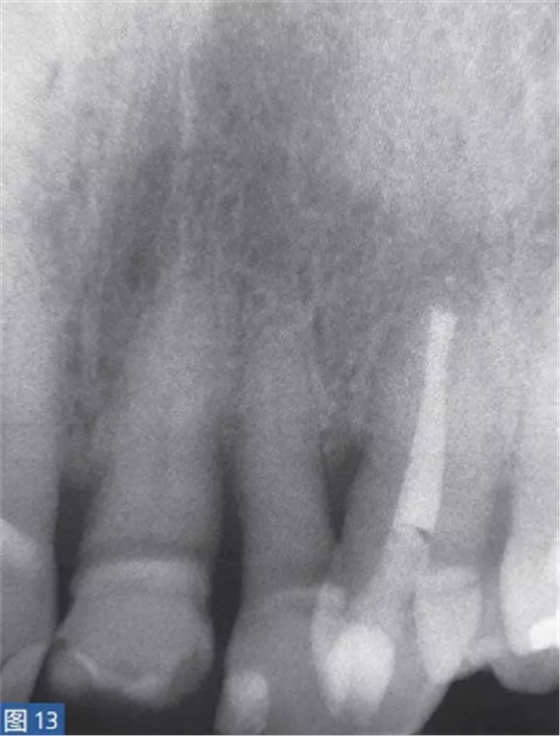

根尖周囊腫伴無癥狀性根尖周炎(AAP)

根尖周囊腫(圖12 和13)總是與無癥狀的根尖周炎相關(guān)。目前普遍認(rèn)為,通過上皮殘留細(xì)胞的炎性增殖形成了根尖周囊腫。在組織學(xué)上,它們分為袋囊腫(pocket cyst)和根尖周真性囊腫(periapical true cysts)。通常認(rèn)為,袋囊腫可以通過單純的根管治療而非手術(shù)方式,即通過細(xì)胞凋亡(apoptosis)和程序性細(xì)胞死亡(programmed cell death)達(dá)到愈合。這種方式在真性囊腫似乎不太可能實(shí)現(xiàn)。

圖12: 23 牙齒根尖周囊腫 。非手術(shù)治療,采取單純的根管治療后的X 線片檢查。因未愈合而決定采取手術(shù)治療。

圖13:手術(shù)性根管治療一年后的對(duì)照X 線片顯示根尖病灶已愈合。對(duì)搔刮出的組織進(jìn)行組織病理學(xué)檢查顯示為真性根尖周囊腫。